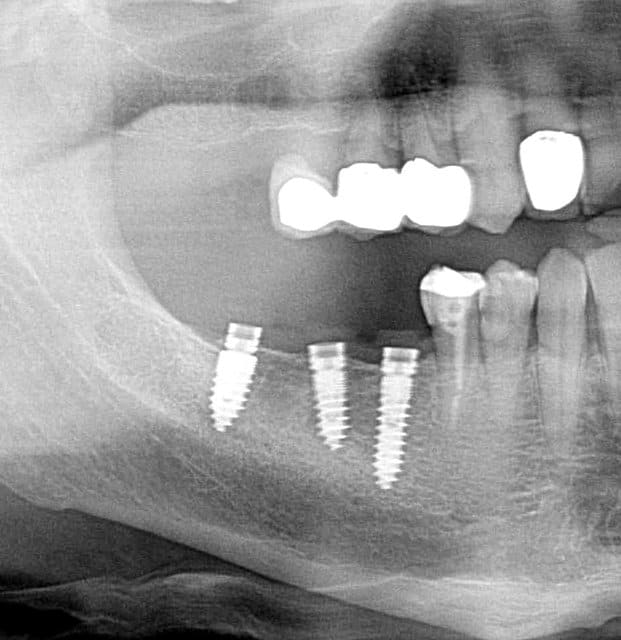

Pour ceux que ca interessent, et parce qu on a m a demandé des cas supplémentaires dans le sujet 23 implants rehabilitation totale, voici un autre cas d implantation immédiate avec la technique minimalement invasive et condensation grace aux forets.

Le patient a reçu un traitement il y a dix ans dans le maxillaire et dans le 4eme quadrant.Comme on peut le voir j´ai du extraire quelques dents au maxillaire: 35 37 et 45.

Le septum de la 37 a été foré avec un foret conique 3 faces.

J ai planté à 60 Ncm sans fracturer le septum.Juste après l opération , les prep caps en zircon ont été cémenté.La restauration définitive 34 jusqu` à 37 été fixé 2 semaines après l implantation avec implantlink (detax). Après un an, le bridge a été retiré facilement pour voir l´état de la gencive et faire une radio de contrôle.On la re ossifiction est satisfaisante et que la gencive "aime" le zircon.

Le bridge a ensuite été recémenté sans correction nécessaire du bridge.